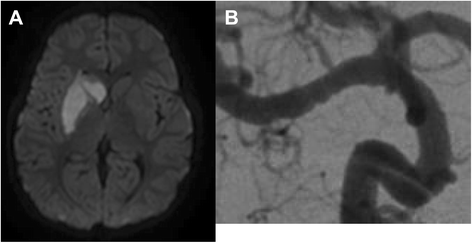

Post stroke-dystonia seems to be much more common among children than adults [6]. A Canadian study found that 21 % of the children with basal ganglia strokes will eventually develop dystonia [9]. This stroke pattern is particularly common in children with focal cerebral arteriopathy (FCA), an important, presumably inflammatory cause of CAIS (Fig. 1). FCA is a unilateral arteriopathy of the large vessels of the anterior circulation, typically affecting the distal ICA and proximal segments of the middle cerebral artery (MCA) and anterior cerebral artery (ACA) [10]. Cerebral infarcts due to FCA are nearly always located in perforator territories within the basal ganglia zone.

Fig. 1

Right basal ganglia stroke (a) due to a focal cerebral arteriopathy involving the M1 segment of the right middle cerebral artery (MCA). Note the beading appearance of the affected MCA segment (b)